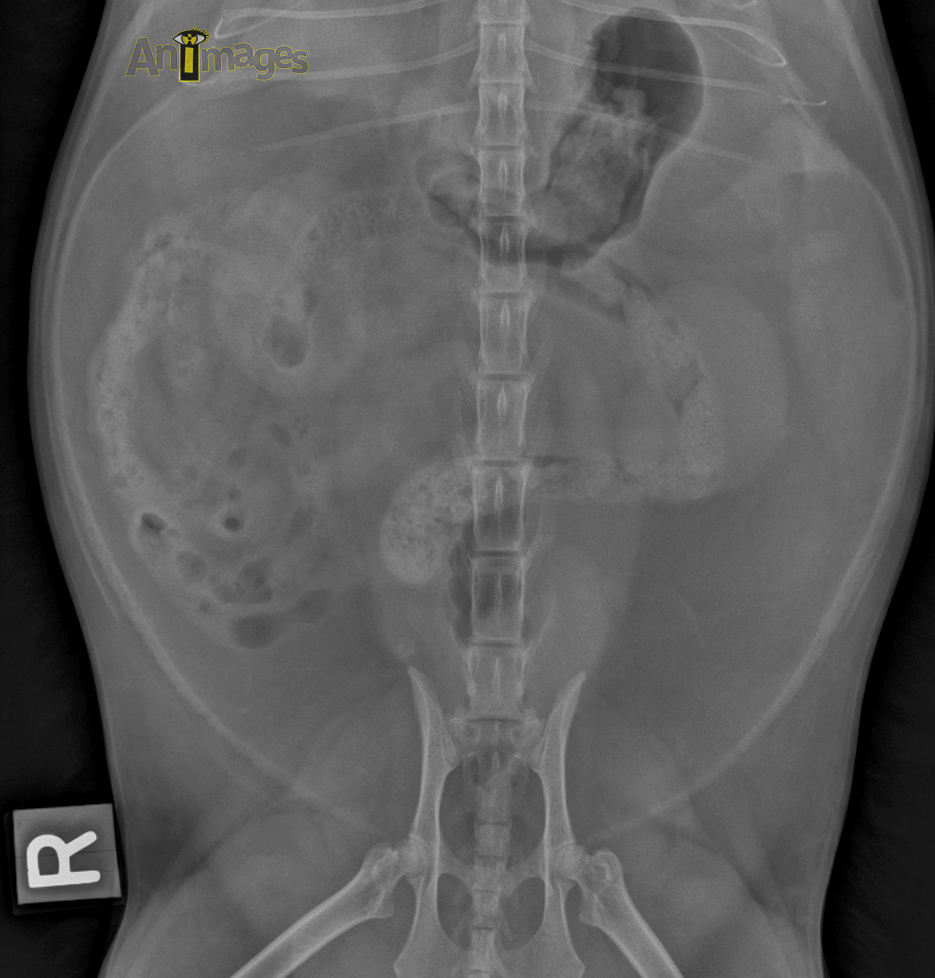

ventrodorsale